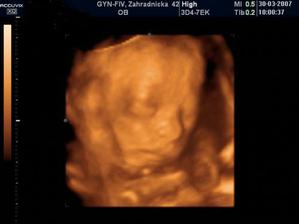

Nathan Nicolas ! bruško, pôrod a prvé mesiace

Nathan Nicolas, narodil sa v Bojnickej pôrodnici, v piatok 13. júla ráno 8:08... Mal 3020 g, 50 cm a spolu so svojim starším bratom je to najväčšie šťastie 🙂